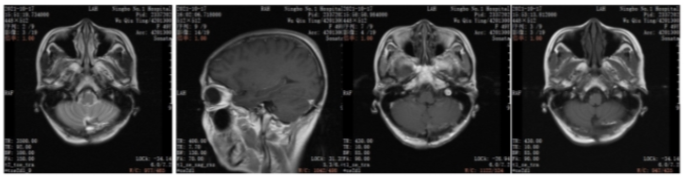

2021年6月颅脑增强MRI:左侧小脑占位,考虑转移瘤。

图2.颅脑增强MRI

2021年6月:出现头晕头痛1周,检查颅脑增强MRI:左侧小脑占位,考虑转移瘤。

2022年5月颅脑增强MRI:左侧小脑肿瘤切除术后改变。

疗效评价CR,继续维持曲妥珠单抗(汉曲优)+吡咯替尼+卡培他滨治疗方案

图3.颅脑增强MRI

本例患者术前评估左乳实性占位(BI-RADS 4c级)。左腋下淋巴结肿大,考虑转移。术后病理:ER(-),PR(-),HER2(3+),Ki67(30%)。由于患者的原因,未能做新辅助治疗,缺失了新辅助治疗后的再一次疗效评估,以及对辅助治疗的进一步决策。术后辅助治疗EC-THP(表柔比星+环磷酰胺,序贯多西他赛+赫赛汀+帕捷特),之后辅助曲妥珠单抗(赫赛汀)+帕妥珠单抗(帕捷特)靶向治疗完成1年治疗。在辅助靶向治疗后4月发现单发脑转移病灶。之后行左侧小脑半球肿瘤切除+颅底重建术。脑转移瘤瘤床区放疗。全身系统治疗:汉曲优+吡咯替尼+卡培他滨作为二线治疗,随访中已有15月的PFS,目前仍是CR状态。